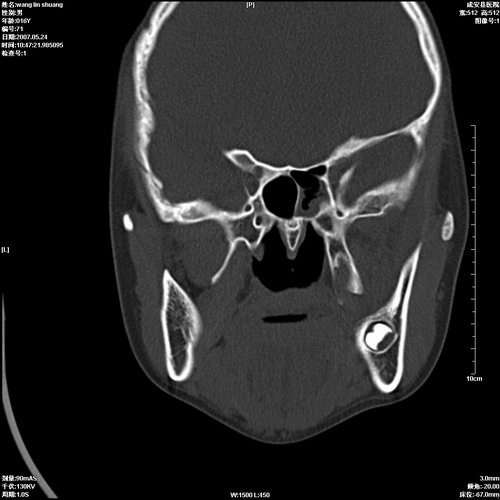

病人,男 16岁,鼻旁右肿胀,其余无不适感,ct图片

1、典型右侧根尖囊肿。

2、双侧上颌窦、筛窦、蝶窦炎

1\\左侧上颌骨含牙囊肿

2\\两上颌窦炎

右侧上颌骨含牙囊肿.双侧上颌窦炎症.

右侧上颌骨含牙囊肿.双侧上颌窦、蝶窦右侧炎症.